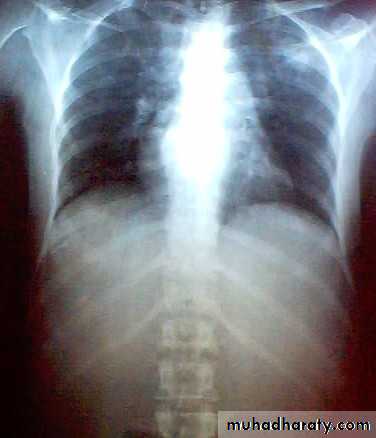

In T B spine

BACKACHE

Kyphosis (gibbus).

Occasionally the presenting feature is weakness or loss of sensibility in the lower limb.

In neglected cases patient presented with paralysis (pott’s paraplegia).